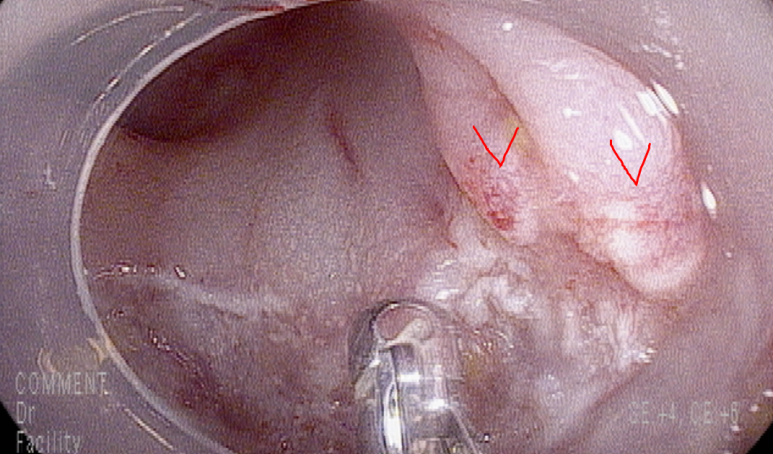

오른쪽 일부분은 스네어로 잡히지 않아 조직겸자로 제거함, 경계 양성 가능성 있으며 양성 종양일 경우 추적검사시 추가적 제거 계획

일부 근육층의 부분적 손상

클립으로 결찰함